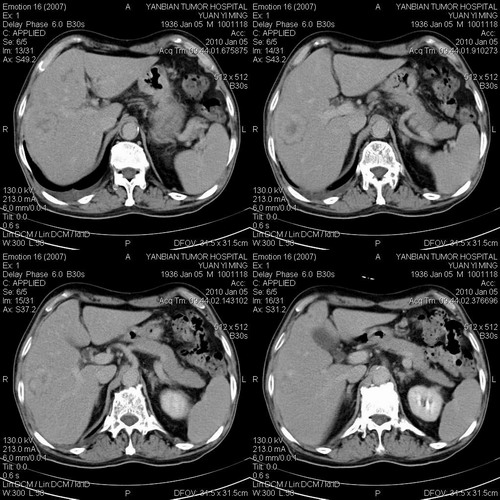

标题: CT24024:男,74岁。体检超声发现肝内多发占位性病变四天。 [打印本页]

标题: CT24024:男,74岁。体检超声发现肝内多发占位性病变四天。

肝癌肝内转移,胃壁增厚,胃癌不能排除

建议查afp。考虑多发结节型肝癌。

考虑多发结节性肝癌。

1)考虑肝脏恶性肿瘤(转移瘤?)。2)肝外胆管轻度扩张。3)左肾小囊肿。